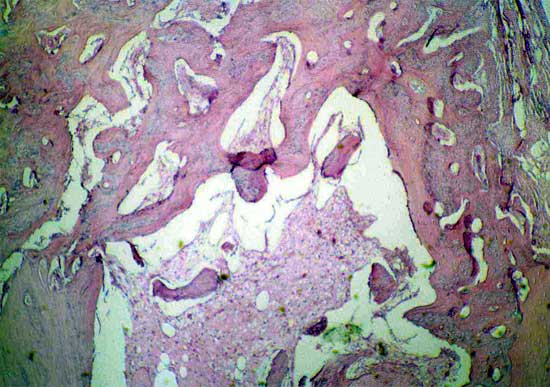

骨髓有核细胞100X                      骨髓有核细胞100X

4周软骨钙化                            骨小梁形成

髓腔形成                              X线4周(BM vs MSC)